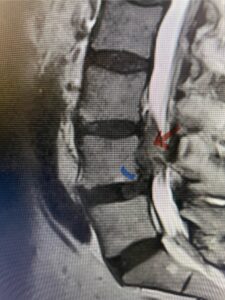

This 54-year-old morbidly obese female presents with progressive back and leg pain and quadriceps weakness. She had no diabetes. She failed all means of conservative management including physical therapy and epidural injections. On imaging she had severe stenosis at L3-4 with a disc protrusion and a slight grade 1 spondylolisthesis at L3-4 (Fig 1). We performed dynamic lumbar x-rays which demonstrated instability at L3-4 and L4-5 (Fig 2). The patient wished to have surgery. We performed an L2-4 decompressive laminectomy and L3-5 in situ fusion because of her instability. Post operatively the patient had relief of leg pain, although the patient was slow to mobilize.

Figs. 1a: Sagittal lumbar T2-weighted MRI demonstrating severe lumbar stenosis with a slight grade 1 at L3-4 and a disc protrusion (red arrow )

Fig. 3a : Sagittal T2-weighted lumbar MRI demonstrating a massive L4-5 disc herniation with superior migration behind the L4 vertebral body and taking up most of the left side of the spinal canal (red arrow) Note the slight grade one spondylothesis at L4-5 (blue dash). Notice the severe compression of the thecal sac (blue arrow) by the large left sided disc herniation (red arrow)